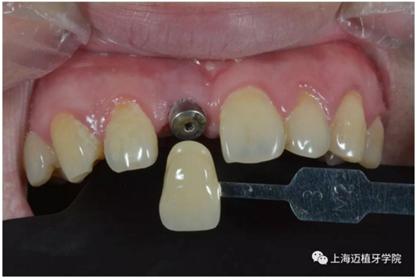

比色:3/M2

氧化鋯個(gè)性基臺(tái)

戴牙前口內(nèi)照片: